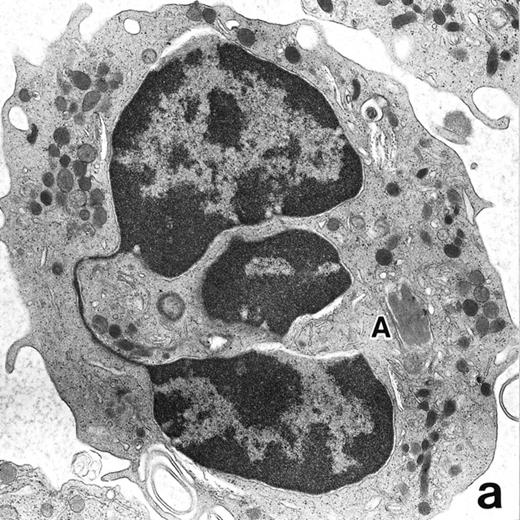

(a) A PMN in patient no. 1, seen in the bone marrow after 3 weeks of ATRA treatment. Lobulated nuclei are connected by nuclear filamentous structures and heterochromatin is highly condensed along the nuclear membrane. An Auer rod (A) is present along with primary granules. (Original magnification × 16,900.) (b) Higher magnification of the cytoplasm of a PMN in patient no. 3 after 3 weeks of ATRA treatment. Auer rods and cytoplasmic granules are all positive for MPO, and no MPO-negative secondary granules are evident. (MPO-stained section, original magnification × 41,900.)